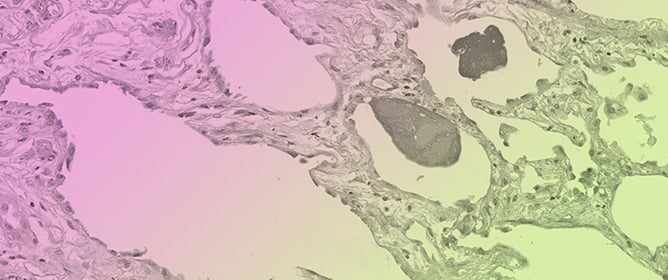

Objectives: To evaluate the diagnostic and prognostic value of histophenotyping of the extracellular matrix of the cervical stroma at cervical intraepithelial neoplasia (CIN). Methods: Retrospective analysis of 160 biopsies and surgical preparations of the cervix in women of reproductive age included cases of

Objectives: To evaluate the diagnostic and prognostic value of histophenotyping of the extracellular matrix of the cervical stroma at cervical intraepithelial neoplasia (CIN). Methods: Retrospective analysis of 160 biopsies and surgical preparations of the cervix in women of reproductive age included cases of CIN 1–3 and the group with confirmed persistence or lesion progression (CIN P) at repeated biopsy. The control group (n = 40) consisted of morphologically intact cervical tissue. Histophenotypes were evaluated by staining with hematoxylin, eosin, and Masson trichrome, and classified as follows: normal (dense parallel bundles of type I collagen), intermediate (disorganized and fragmented type I collagen fibers), and myxoid (amorphous weakly fibrillar matrix). The clinical, viral, and inflammatory characteristics between histophenotypes were statistically compared. Results: The distribution of histophenotypes of the extracellular matrix of the cervix varied significantly depending on the CIN degree (p < 0.001). In the control group, the normal pattern was detected in 97.5% of cases; its frequency decreased from CIN 1 (27.5%) to CIN 2 (12.5%) and was absent at CIN 3. The frequency of the myxoid pattern increased significantly in severe and persistent forms: 55% at CIN 3 and 62.5% at CIN P. Human papillomavirus 16/18 was most frequently detected in groups with intermediate (69.1%) and myxoid (27.2%) patterns. Inflammatory changes were more often accompanied by disorganized extracellular matrix; however, intermediate and myxoid types also occurred in the absence of inflammation. Conclusions: The myxoid histophenotype of the extracellular matrix is significantly associated with the high degree of dysplasia and CIN persistence. It can reflect the morphological equivalent of tumor-associated stroma remodeling. Histophenotyping of the extracellular matrix of the cervix appears to be a promising method of risk stratification and may complement existing diagnostic algorithms for CIN.

Figure 1